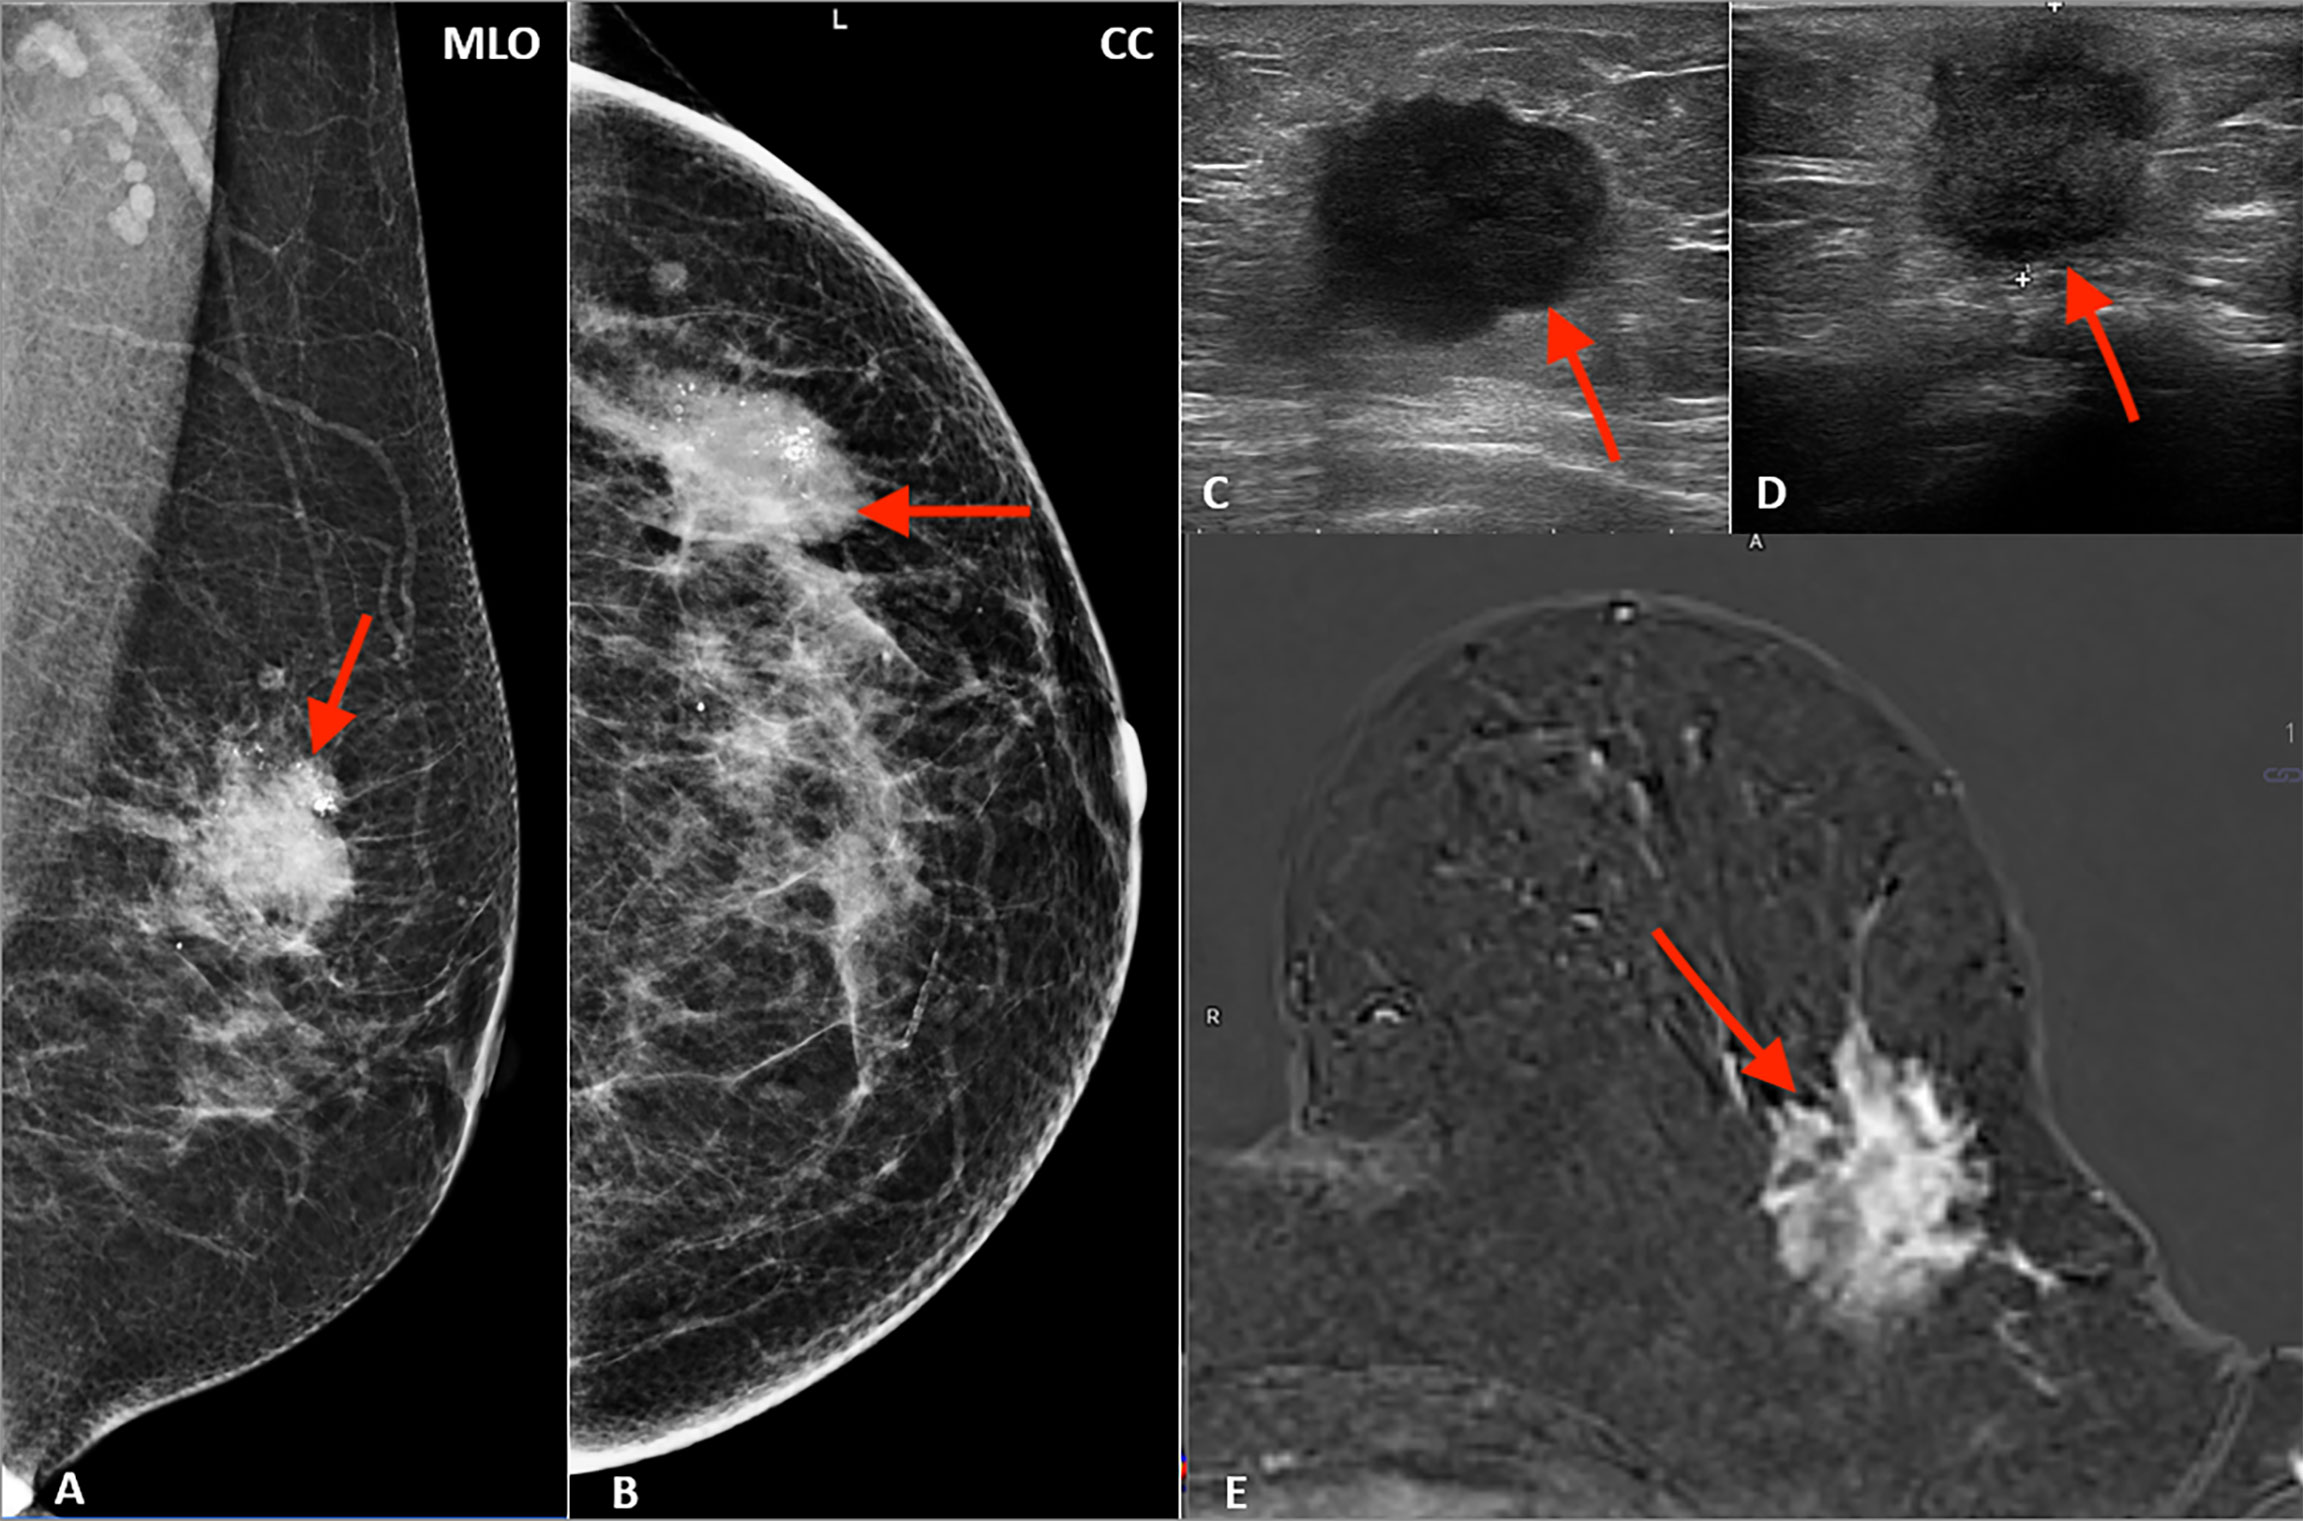

शरीरका अन्य अंगहरूजस्तै स्तन पनि विशेष कार्यका लागि बनाइएका कोषहरूले बनेका हुन्छन् । बाहिरी भागमा भएकोले स्तनमा देखिने परिवर्तन चाँडै थाहा पाउन सकिन्छ । स्तनमा कुनै प्रकारको अनावश्यक कोष वृद्धि भयो भने त्यो गाँठो (ट्युमर) बन्न सक्छ । सबै गाँठो क्यान्सर हुनेचाहिँ होइनन्, करिब १० प्रतिशतमात्र क्यान्सरग्रस्त हुने सम्भावना हुन्छ । तर पनि कुनै पनि गाँठो देखिएमा चिकित्सकको सल्लाह लिनु अत्यावश्यक हुन्छ ।

स्तन क्यान्सरको सुरुको अवस्थामा कुनै पनि लक्षण देखा पर्दैनन् । सामान्यतया दुख्न पनि दुख्दैन । विभिन्न जाँचहरूबाट मात्रै यस अवस्थाको क्यान्सर पत्ता लाग्दछ । हाम्रो समाजमा केही समस्या नभई स्वास्थ्य परीक्षण गराउने चलन छैन । जब क्यान्सर बढ्न थाल्छ, यसले स्तनमा परिवर्तन ल्याउँछ, जसलाई एउटी महिलाले थाहा पाउन सक्नेछिन् । स्तन अथवा काखीमा प्राय: नदुख्ने साह्रो गाँठो हुनु स्तन क्यान्सरको मुख्य लक्षण हो । अन्य लक्षणहरूमा स्तनमा निको नहुने घाउ हुनु, दूधको मुन्टोबाट असामान्य चिज बग्नु, स्तनमा दुख्ने गाँठो तथा दूधको मुन्टोमा परिवर्तन आउनु अथवा कहिलेकाहीँ झरेर जानु आदि लक्षण हुन् ।